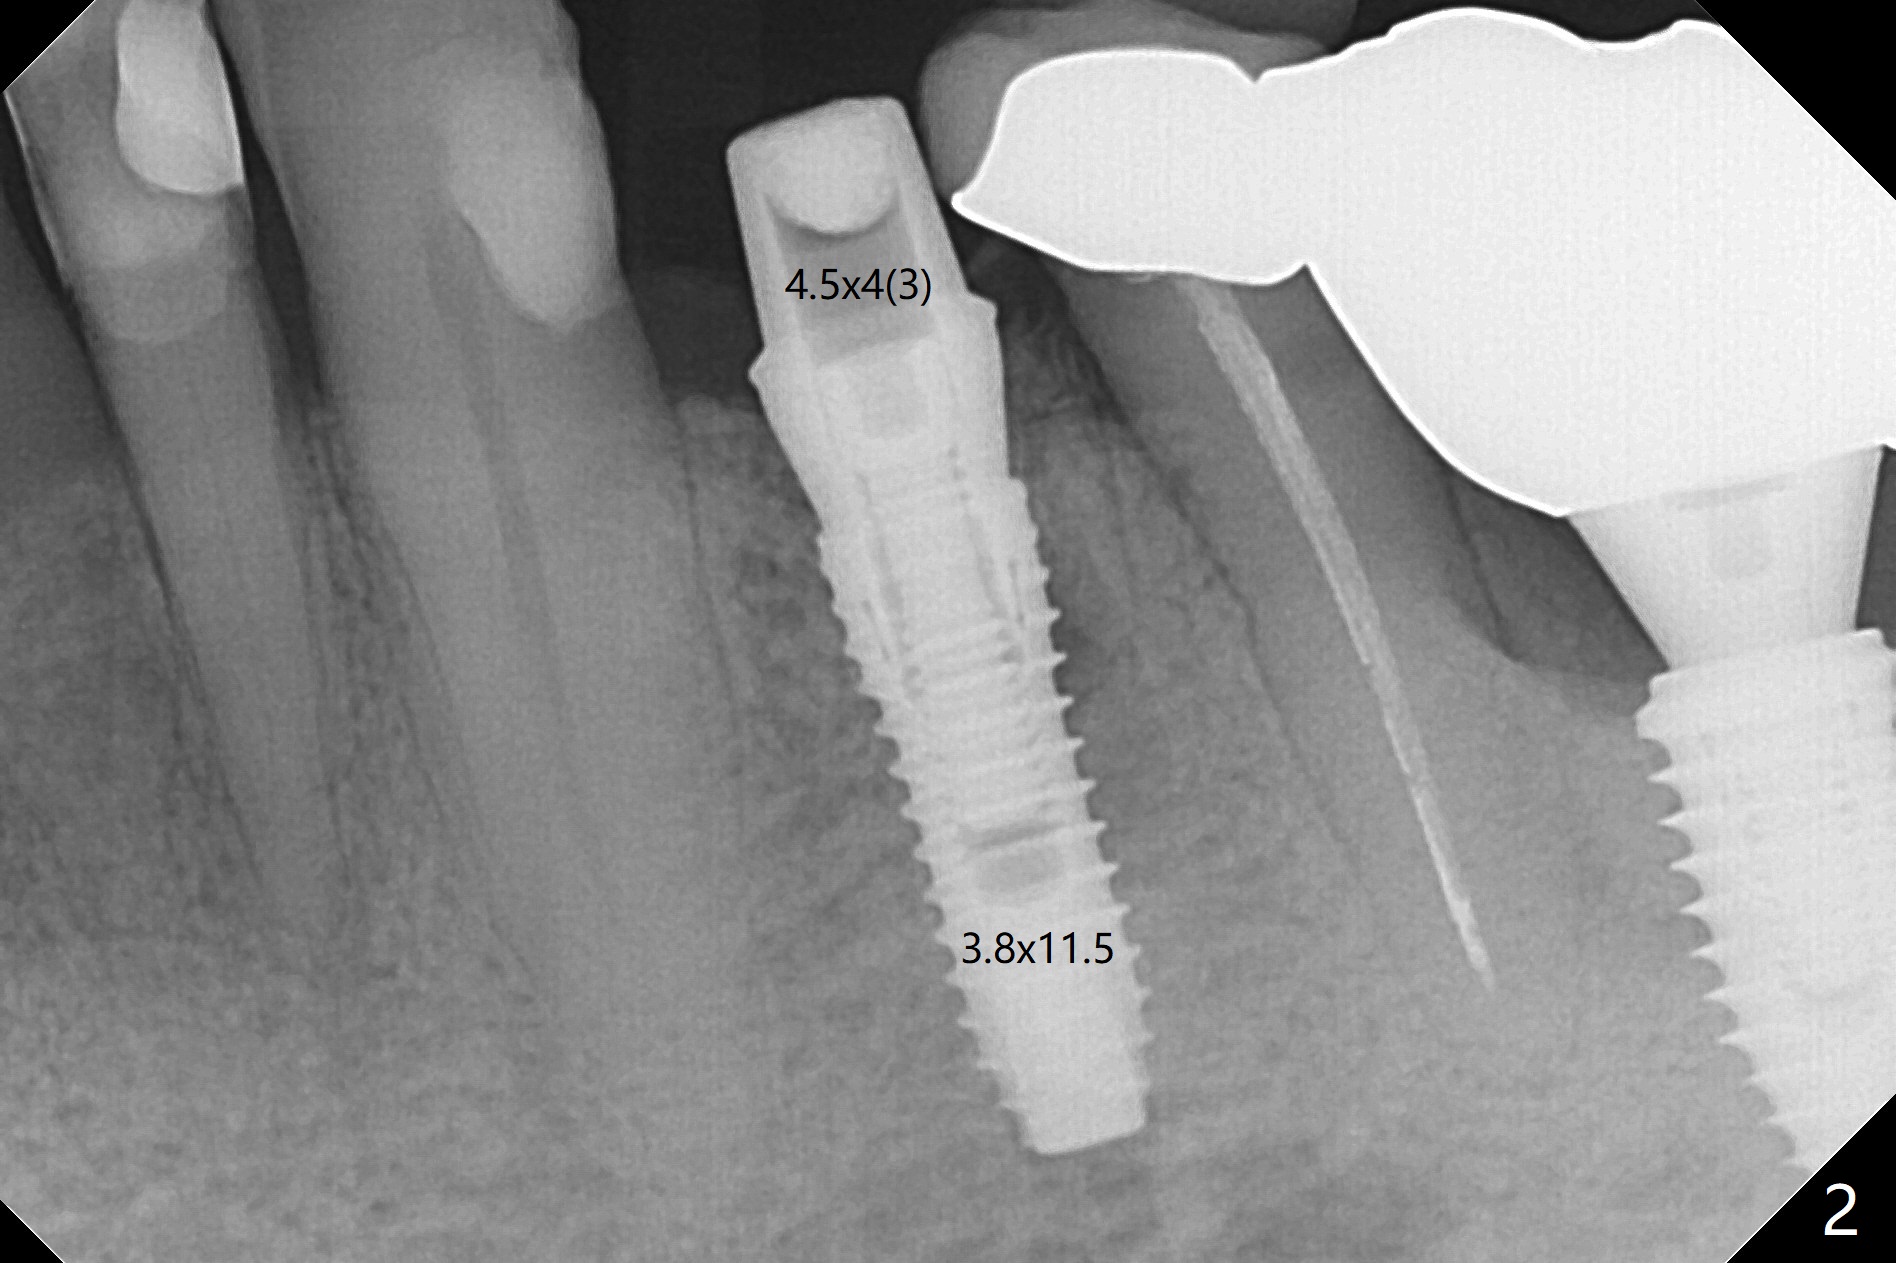

Extraction of the fractured tooth at #21 is as difficult as #19 (requiring incision). Because of the long root and hemorrhage, the apex of the tooth (Fig.1 black *) and a thin layer of the buccal shield (white *) remain when osteotomy is initiated. Due to hard bone, a 3.8x11.5 mm implant achieves insertion torque of ~35 Ncm (Fig.2); with placement of a 4.5x4(3) mm abutment, an immediate provisional is fabricated. There is limited remaining space for bone graft. The patient will return for final restoration 4 months postop; the buccal plate will be expected to have not collapsed! The implant seems to be osteointegrated, while the root piece (socket shield *) is exposed 4 months postop (Fig.3). The socket shield seems to be harmless, difficult to trim without local anesthesia and associated with no buccal plate concavity (Fig.4,5 <). With socket shield at #21, the crown looks normal, whereas the one at #19 without socket shield looks long, suggesting vertical bone loss early postop (before restoration, Fig.6).没有牙根处,角化龈少(图七,与术前(图八)对比)。